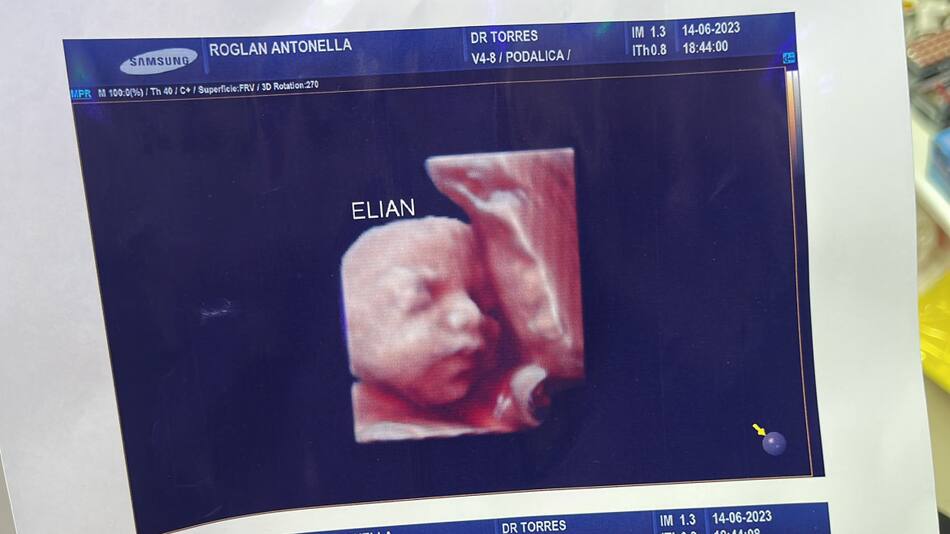

Insólita denuncia se realizó en Formosa. Una clínica privada fue demandada por realizar falsas ecografías 5D y entregar la misma foto a varias de sus pacientes embarazadas. El hecho se descubrió gracias a un posteo en sus redes sociales, donde dos mujeres notaron que tenían el mismo material entregado.

A través de su cuenta de Instagram, una usuaria publicó la foto del rostro de su hijo en camino. Sin embargo, apareció otra mujer para advertirle que ese no era su hijo y le mostró la imagen que creía era del bebé que ella gestaba. Allí ambas notaron que era exactamente el mismo retrato.

Denuncian a una clínica por entregar la misma foto de la ecografía 5D a todas las pacientes. Foto: Twitter.

"Ay noo, es la misma", escribió en un mensaje privado que sirvió como disparador para la denuncia contra el instituto de salud. Ambas le dijeron al medio Noticias de Formosa que asistieron al mismo lugar y hasta dieron detalles de cómo era el proceso. "Al llegar, te tomaban los datos, ingresabas a una sala donde te hacían la ecografía y luego de unos minutos la secretaria te entregaba en informe impreso”, comentaron.

Claro que el caso tomó mucha relevancia en poco tiempo, en especial en las redes sociales. A través de Twitter, una de las mujeres que fueron perjudicadas mencionó: "Por ahora somos tres mamás a las que una clínica estafó con una foto de un bebé que no es el nuestro".

Algunas de las pruebas que subieron las mujeres estafadas. Foto: Twitter.

"Está de más decir que encima que cobran carísimo, uno se va ilusionado por ver a su bebé y tener un lindo recuerdo. Estamos en busca de más mamás con el mismo bebé", siguió sobre el triste hecho que le tocó atravesar. Mientras se espera que en las próximas horas se haga la denuncia formal en la sede judicial, la clínica se mantiene en silencio sobre lo ocurrido.